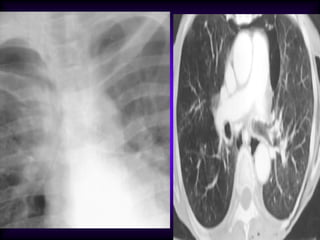

Consolidation Right

Upper Lobe /

Density in right upper lung

field

Lobar density

Loss of ascending aorta

silhouette

No shift of mediastinum

Transverse fissure not

significantly shifted

Air bronchogram